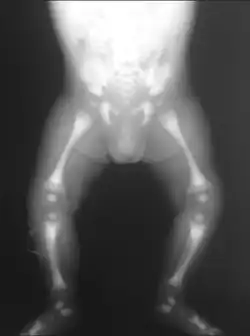

Adult-onset osteopetrosis (Albers-Schönberg Disease)

X-ray of the pelvis of a patient with osteopetrosis, adult onset form (Albers-Schönberg disease). Note the dense appearance.